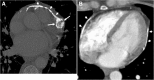

The pericardium could be involved in a variety of clinical disorders. The imaging findings are not specific for an individual pathology in most of the cases; however, patient's clinical history may guide radiologist to a definitive diagnosis. Congenital absence of the pericardium could be recognized with the imaging appearance of interposed lung tissue between the main pulmonary artery and aorta. Pericardial effusion is a non-specific condition that may occur due to inflammatory, infectious, and neoplastic disorders. Cardiac tamponade may occur in case of massive or rapid accumulation of fluid in the pericardial sac. Pericardial calcification is a common and easily identified entity on a computed tomography (CT) scan. Presence of calcification and/or fibrosis may result in pericardial constriction. Nevertheless, the pulsation of an adjacent coronary artery may prevent calcification formation in a focal area and consequently may result in pericardial diverticulum containing epicardial fat and coronary artery. The imaging findings encountered in patients with pericardial hydatid disease and Erdheim-Chester disease may mimic those of pericardial neoplasia. Pericardial adhesions and pedicled fat flaps may cause confusion on a CT scan in the post-surgical period following cardiac surgery. Pericardial fat necrosis can be diagnosed by CT in patients with chest pain. The radiologists should be familiar with the medical devices placed in pericardial space for certain individual indications. A pericardial patch and temporary epicardial pacemaker wires could be identified on a CT scan.